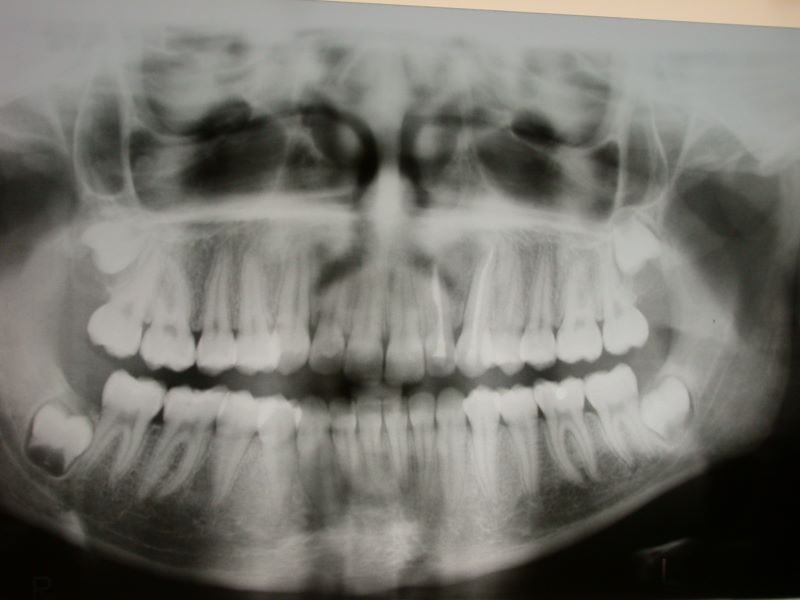

La diagnosi dell’atrofia ossea mascellare inizia tipicamente con un esame dentale completo. Durante questo esame, il dentista può notare segni di perdita ossea, come la recessione gengivale o la mobilità dei denti.

Per confermare la diagnosi e valutare l’entità della perdita ossea, il dentista può utilizzare tecniche di imaging come la radiografia o la tomografia computerizzata a fascio conico (CBCT). Queste immagini dettagliate permettono al dentista di vedere l’osso sottostante e di misurare la quantità di osso rimanente.